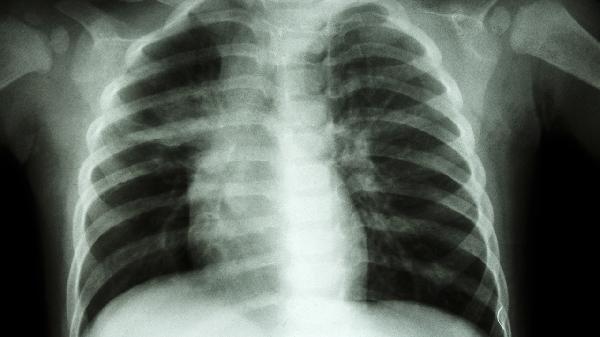

按疗程规范用药,通常需连续服用3个月以上,突然停药可能影响疗效。治疗期间每2个月复查胸片及肺功能,医生评估后决定是否调整方案。症状缓解后仍须完成剩余疗程以防复发。